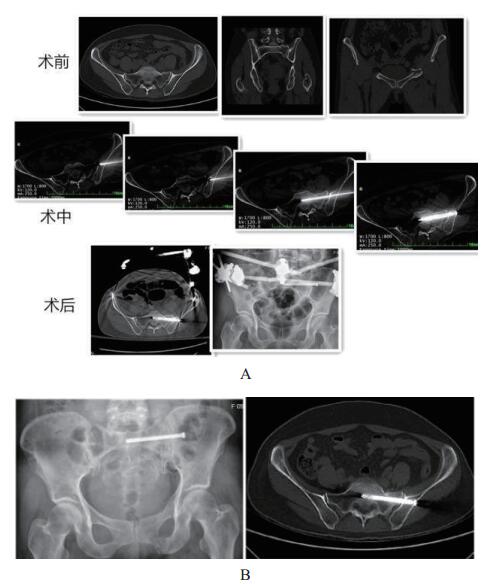

2.2 随访结果平均随访时间15.2个月(8~21个月)。所有的骨折均愈合,没有螺钉相关并发症,无血管神经并发症,切口愈合良好。12例患者使用了前环外固定支架(其中3例髂前下棘,9例髂嵴);4例前环重建钢板固定;3例髋臼骨折使用重建钢板固定。7.3 mm空心钉16根;6.5 mm空心钉3根;6根用了垫圈,空心钉长度平均为72 mm(55~85 mm)。由于是微创手术,所以出血量很少,难以准确计量。术后患者骨盆引起的疼痛均能得到明显缓解,末次随访的VAS评分平均为1.8。骨折复位情况通过Matta评分标准,优:14例,良:4例。功能评分采用Majeed评分标准,末次随访评分,优:11例,良:6例,可:1例,患者基本回到原来工作及生活。(典型病例见图 3,4)

|

| 图 3 患者,女,53岁,左侧骶骨骨折伴耻骨上下支骨折,术中置钉移动CT扫描4次,术后显示置钉位置好(A)。随访显示骨折愈合好(B)。 |

| 图 4 患者,女,53岁,左侧骶骨骨折伴耻骨上下支骨折,术中置钉移动CT扫描4次,术后显示置钉位置好(A)。随访显示骨折愈合好(B)。 |